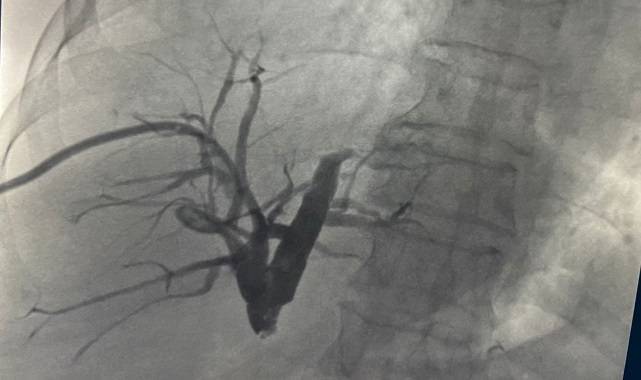

Endobiliyer Radyofrekans (RF) ablasyon ile tümörler, yakılarak tedavi ediliyorProf. Dr. Ercan Kocakoç, bu yeni yöntemin tıp literatürüne Radyofrekans (RF) ablasyon olarak geçtiğini belirtti. Başta karaciğer olmak üzere vücudun birçok bölgesindeki tümörlerin ultrason, tomografi gibi görüntüleme yöntemlerinin kılavuzluğunda yakılarak tedavi edebilen, girişimsel radyolojik bir yöntem olduğunu söyledi. Prof. Dr. Ercan Kocakoç, önce safra kanalı içerisine basitçe ince plastik bir hortum yerleştirilerek, biriken safra sıvısının dışarıya alındığını dile getirdi. “Tümörün olduğu bölgedeki darlık, bir tel yardımıyla geçilebilirse önce balon ile bu bölge genişletilmeye çalışılır. Sonrasında ise stent denilen ince tellerden örülü metalik bir küçük borucuk yerleştirilerek dışarıda hortum olmadan safranın on iki parmak barsağına akması sağlanır.” açıklamalarını yaptı.Prof. Dr. Ercan Kocakoç ayrıca safra yolu kanserlerinin tedavisinde Endobiliyer RF ablasyon yöntemi ile de safra kanalı içerisindeki tümörün RF ablasyon ile yakıldığını kaydetti. Prof. Dr. Ercan Kocakoç, “Bu yöntemde safra kanalındaki darlığın balon ile açılması, safra kanalı içerisinden RF (radyofrekans) ablasyon ile tümörün yakılması ve safra kanalına metalik stent yerleştirilmesi aşamaları vardır. Bu işlem safranın on iki parmak bağırsağına akmasını sağlayarak sarılıksız daha uzun bir ömür geçirilmesine katkı sağlar.” şeklinde konuştu.

75 yaşındaki hastamız, 1 hafta içinde normale döndüProf. Dr. Ercan Kocakoç en son, 75 yaşında yurtdışından sarılık şikâyeti ile gelen, ana safra kanalında tümör bulunan ve ciddi kalp yetmezliği nedeniyle ameliyatı riskli olan bir hastasına bu yöntemi başarıyla uyguladıklarını dile getirdi. Yaklaşık 11 ay önce genel anestezi verilmeden sedasyon ile endobiliyer RF ablasyon tedavisi ve stent yerleştirilmesi işleminin gerçekleştirildiğini açıkladı. Sarılığı yaklaşık 1 hafta içerisinde normale dönen hastamız halen sarılık şikâyeti olmaksızın hayatına devam etmektedir.Tüketici TV